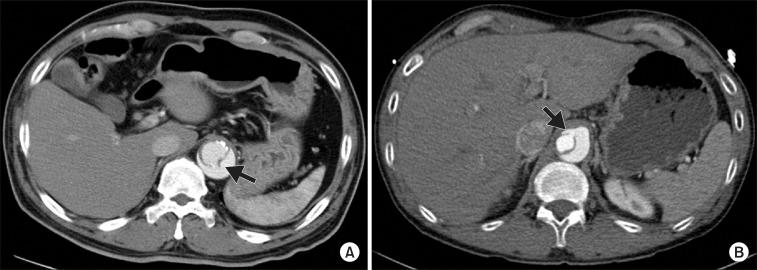

METHODS

This study enrolled 41 patients (age, 55.2±11.9 years) who were evaluated with dual-source computed tomography (CT) imaging of the whole aorta in the setting of the surgical repair of acute type I AD. Logistic regression models were used to determine the predictors of a composite of the aortic aneurysm formation (diameter >55 mm) and rapid aortic expansion (>5 mm/yr).

RESULTS

On initial CT, a distal re-entry tear was identified in 9 patients. Two patients failed to achieve proximal tear exclusion by the surgery. Serial follow-up CT evaluations (median, 24.6 months; range, 6.0 to 67.2 months) revealed that 14 patients showed rapid expansion of the descending aorta or aortic aneurysm formation. A multivariate analysis revealed that the residual intimal tear (odds ratio [OR], 4.31; 95% confidence interval [CI], 1.02 to 19.31) and the patent false lumen in the early postoperative setting (OR, 4.64; 95% CI, 0.99 to 43.61) were predictive of the composite endpoint.

CONCLUSION

The presence of a residual intimal tear following surgery for acute type I AD adversely influenced the expansion of the descending aorta.